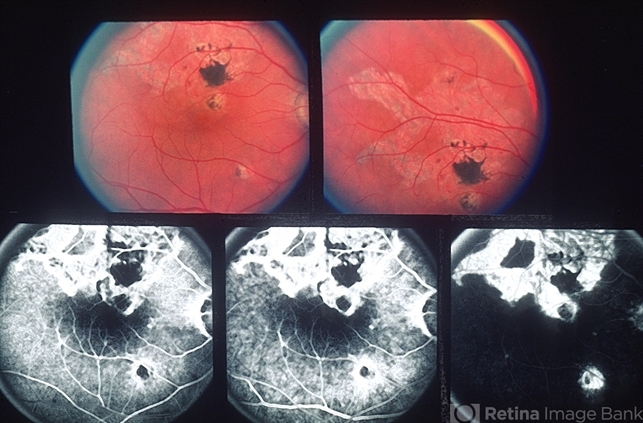

- subretinal neovascularization (SRNV), geographic helicoid peripapillary choroidopathy (GHPC)

- 57-year-old white male, GHPC-SRNV, 20/40; 1/200.